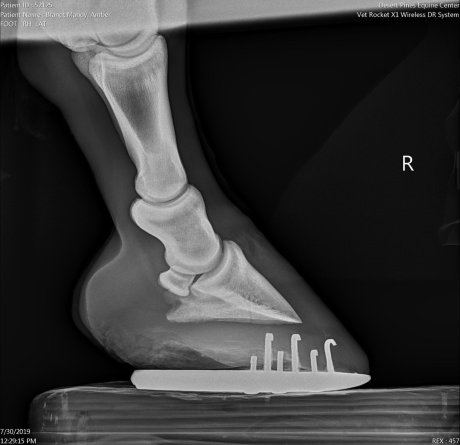

To looking like this:

You can bet I’m feeling pretty damn good about that. Just a big breath of relief. Looks like we’ve found a perfect angle, and having shoes on the hind feet and a pad is all just the right mix for her. That’s A LOT of sole that she grew, which is super positive. Even Doc said that in all her x-rays she’s never grown this much hoof, which is excellent. A definite “yes” that we’re on the right track again! I know she’s happy – she really really hated those boots lol.

Doc also said that she’ll probably have a very normal-looking foot. While that’s a plus, I’m certainly not too worried even if it’d look abnormal. It’d just get trimmed in the way it functioned the best. It’s still a positive, though, so you can bet that I’m taking that too haha! Her front feet are looking positive as well, and I think she’s a lot more comfortable.